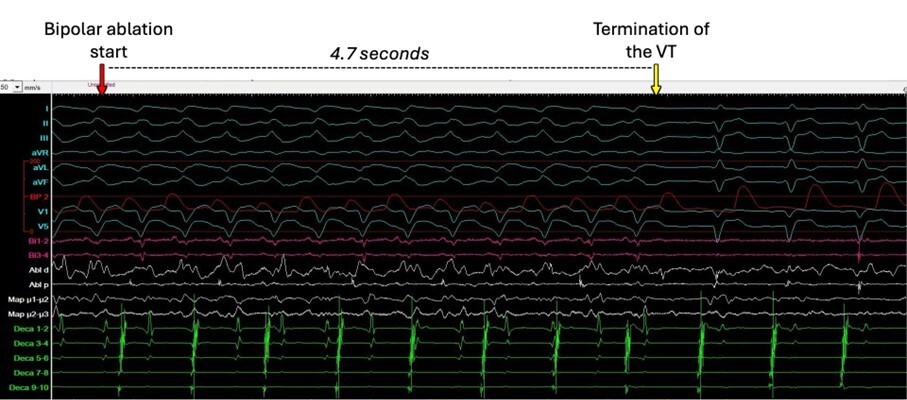

Die Untersuchung erfolgte unter Kardioanalgosedierung mit Propofol und Fentanyl. Das Voltage Map des LV im Sinusrhythmus zeigte ein ausgedehntes Areal mit Niedervoltage anterolateral und apikal sowie Nachweis von Spätpotentialen (Abb. 2A). Durch programmierte Stimulation konnte die klinische Tachykardie induziert werden (Morphologie: inferiore Achse, negative V1-V6, negative I; Abb. 1).

12-Kanal-EKG der ventrikulären Tachykardie (50 mm/s)

Abbildung 1: 12-Kanal-EKG der ventrikulären Tachykardie (50 mm/s)

Bei somit ein ehesten intramuralen Abschnitt des Reentry-Kreises (Abb. 4C) entschlossen wir uns zur Durchführungen einer bipolaren Ablation getroffen. Diese erfolgte mit zwei gespülten Kathetern: der aktive Katheter wurde epikardial positioniert an der Lokalisation des potenziellen Isthmus anteroapikal mit einem Anpressdruck von 23 Gramm und der passive Ablationskatheter („Neutrale“) wurde endokardial gegenüber des epikardial liegenden Katheters positioniert (Abb. 2 D und E). Der Adapter für bipolare Ablation (CorSystem, Rzeszow, Polen) wurde verwendet. Die initiale Impedanz bipolar war 145 Ohm. Die bipolare epi-endokardiale Ablation erfolgte mit 40 Watt. Dies führte zur Terminierung der VT nach 4.7 Sekunden nach Ablationsbeginn (Abb.3).

Start der bipolaren Katheterablation und Terminierung der VT nach 4.7 Sekunden.

Abbildung 3: Start der bipolaren Katheterablation (roter Pfeil) und Terminierung der VT (gelber Pfeil) nach 4.7 Sekunden. CS, Koronarsinus; Abl, "aktiver" Ablationskatheter epikardial; Bi, "passiver" Ablationskatheter endokardial